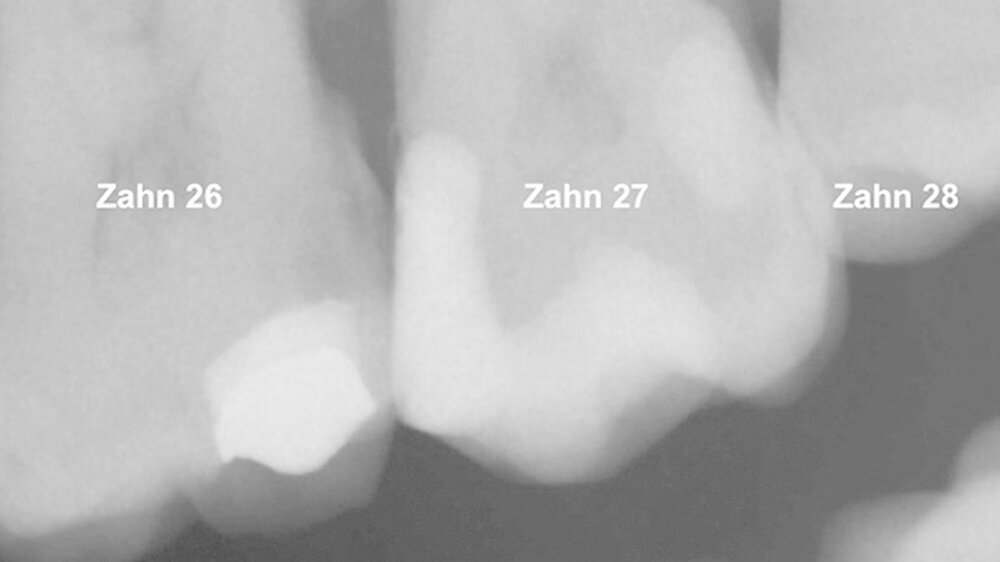

Ein 72-jähriger Patient stellte sich im Oktober 2013 zu einer Routinekontrolle in der Poliklinik für Zahnerhaltung und Parodontologie der Universität Regensburg vor. Bei der Befunderhebung wurde aufgrund des Verdachts auf Approximalkaries eine Röntgenaufnahme im Bereich des zweiten Quadranten angefertigt. Im Bereich des Zahns 26 distal wurde eine "Caries profunda“ diagnostiziert (Abbildung 1) und daher ein Termin zur Füllungstherapie vereinbart.